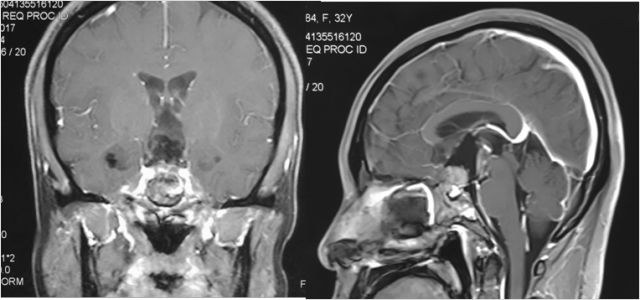

听神经瘤

手术体位个性化选择

术前

术后